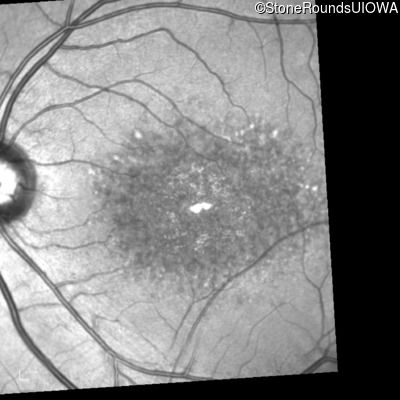

Infrared Fundus Photograph - Right - 10/125 -1

Exemplar

Infrared Fundus Photograph - Left - 10/125 -1